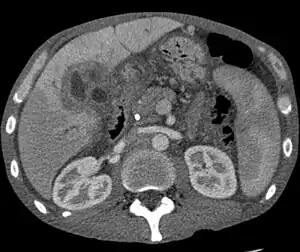

CT scan of a liver with cholangiocarcinoma